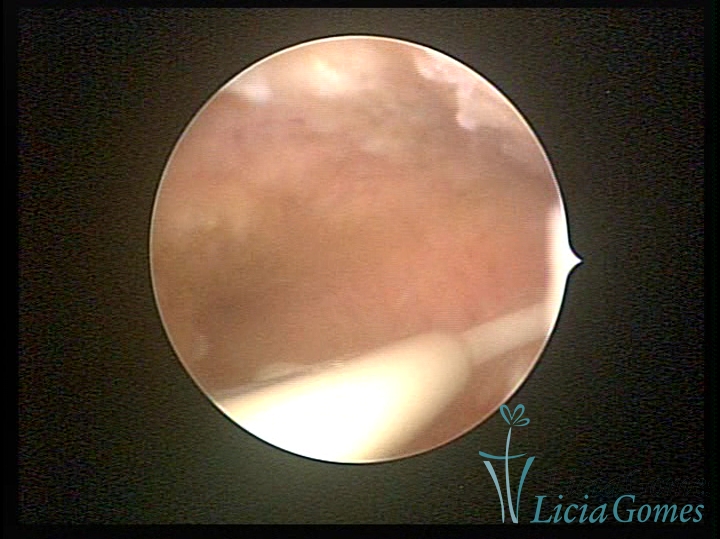

Cervical canal with IUD string